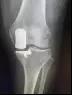

近年来,微创、保膝的理念逐渐被大家所接受。微创单髁置换手术就是微创保膝理念的有效解决办法之一。它也叫做部分膝关节置换术,手术只是将膝关节内侧部分磨坏的股骨和胫骨骨头切除,装上非常耐磨的人工材料,保留外侧未磨损的关节和关节内所有韧带。而且手术可以通过比全膝置换小得多的伤口来完成,其创伤小、出血少、恢复快、假体寿命长、功能恢复程度高等一系列优点正逐步的显示在世人眼前。

全膝关节置换大切口(下)

全膝关节置换大切口